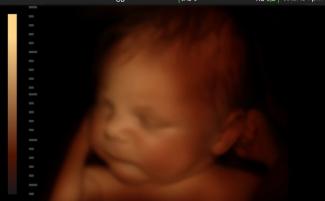

Štát prijal ďalšie obmedzenia interrupcií pod vedením guvernéra Rona DeSantisa, republikánskeho kandidáta na prezidenta v roku 2024. Ten sa postavil proti financovaniu interrupcií z daňových dolárov a tiež podpísal zákon, ktorý zakazuje interrupcie po zistení srdcového tepu dieťaťa’zvyčajne v šiestich týždňoch.